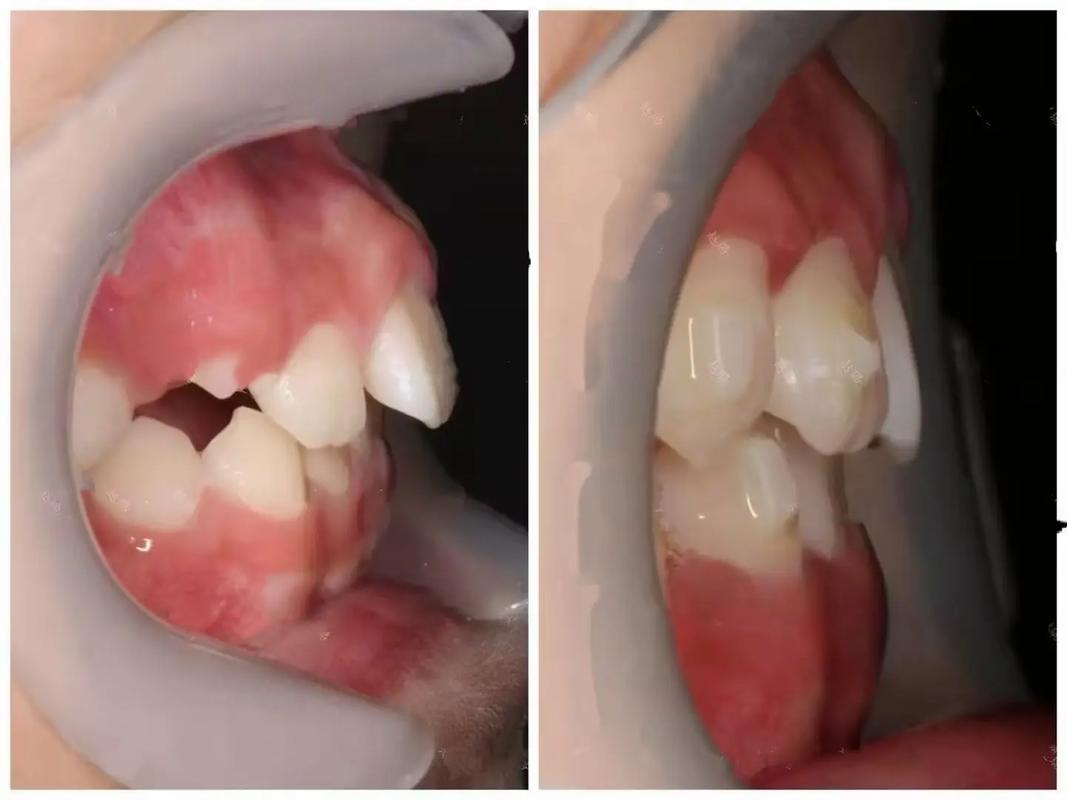

从临床表现看,上牙外凸可分为牙性和骨性两类,牙性上牙外凸主要表现为牙齿排列异常,牙列整体向前倾斜,但颌骨形态基本正常,患者面部轮廓无明显改变,笑时上唇过度紧张,牙龈暴露较多(露龈笑);骨性上牙外凸则涉及上颌骨发育过度,或下颌骨发育不足,导致面部中份突出,侧面观呈“凸面型”,严重者可能伴随颏部后缩、上下唇闭合困难、张口呼吸等问题,且单纯正畸矫正效果有限,常需配合正颌手术。

具体而言,牙性上牙外凸主要通过“牙齿移动”实现:通过弓丝、托槽、支抗钉等装置,将上前牙整体向舌侧移动,同时控制牙根位置,避免过度倾斜;若存在牙弓狭窄或拥挤,可能需配合扩弓或拔牙(如拔除第一前磨牙)为牙齿内收提供空间,骨性上牙外凸则需“颌骨调控”:对于青少年患者,可利用生长发育潜力,通过功能矫治器(如FRⅢ矫治器、前方牵引装置)抑制上颌骨过度生长,促进下颌骨发育;对于成年骨性患者,正畸治疗主要目的是为正颌手术做准备(如排齐牙齿、调整咬合),术后再通过正畸精细调整咬合关系。